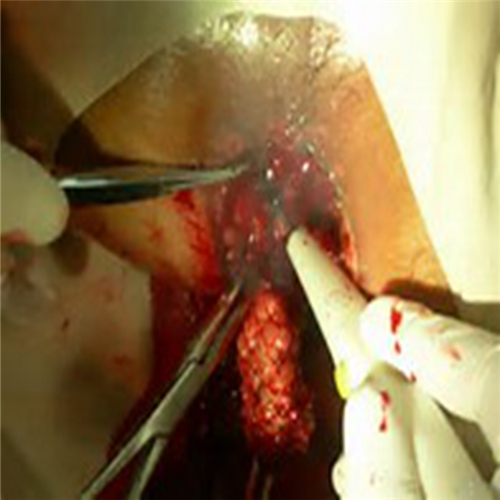

直腸息肉手術過程

直腸息肉割除手術